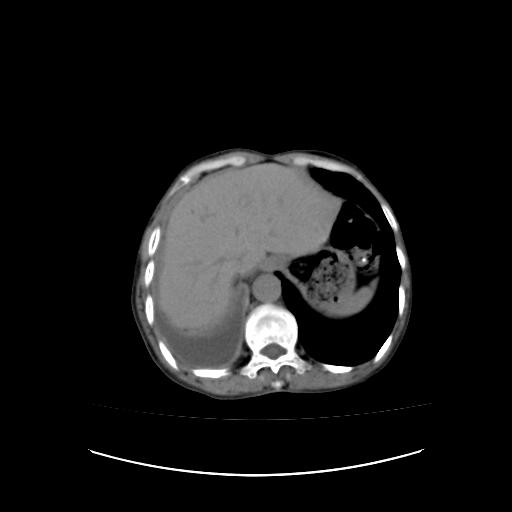

右侧胸膜增厚,局部呈结节状增厚,右侧胸腔少量积液。双肺未见确切肿块影。纵隔未见淋巴结肿大。气管、支气管通畅。考虑右侧胸膜间皮瘤(恶性?)可能性大。不除外癌性胸膜炎。

右侧胸廓塌陷,右侧胸膜广泛增厚并见多发胸膜结节,右侧少量胸腔积液并包裹。

右侧广泛胸膜增厚,局部呈结节状增厚,右侧胸腔少量积液。双肺未见确切肿块影。纵隔未见淋巴结肿大。气管、支气管通畅。考虑右侧胸膜间皮瘤(恶性?)可能性大。支持!